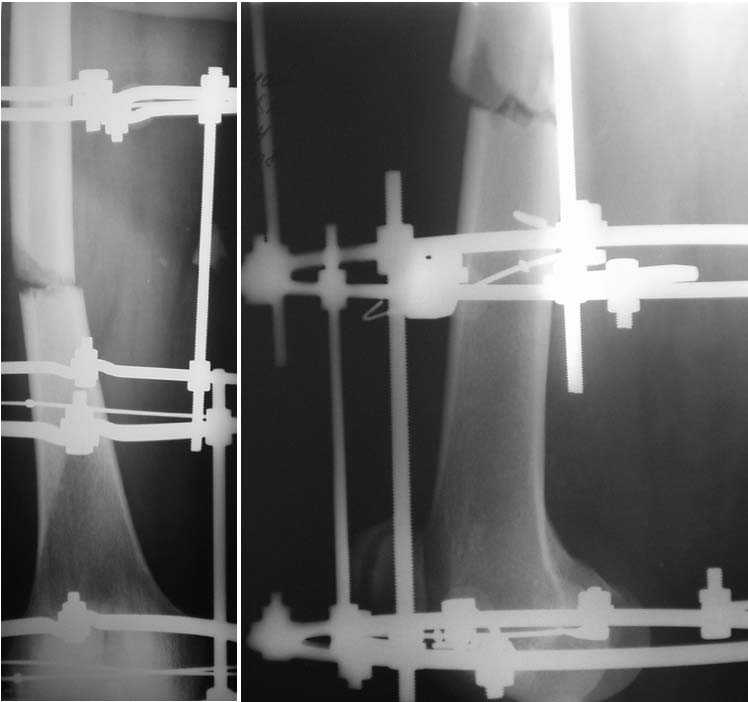

Мужчина, 44 г. Травма в ДТП 22.08.08: открытый перелом ср\3 диафиза правой бедренной кости, закрытый оскольчатый перелом правого локтевого отростка со смещением, в\3 правой лучевой кости со смещением, закрытый перелом верхушки внутренней лодыжки правой голени.

Находился на лечении в одной из городских больниц (где в ургентном порядке произведена операция - ПХО ран, ЧКО правого бедра аппаратом спице-стержневого типа, иммобилизация правого предплечья гипсовой повязкой). Переведен для дальнейшего лечения в ДНИИТО. Через 18 дней после травмы выполнены рентгенограммы таза - диагностирован перелом шейки бедра. На данный момент раны бедра заживают вторично с участками некроза.

Male, 44 y.o. Trauma in MVA 22.08.08: open fracture of right femur (middle shaft), close fractures of right elbow and pilon.

He was in rural hospital were debridgement and Ilizarov frame for femur were performed. Now, he is in Regional Trauma Hospital. After 18 days of trauma x-ray of pelvis were performed – fracture of right femur neck. Wounds at femur is healing with small points of necrosis.